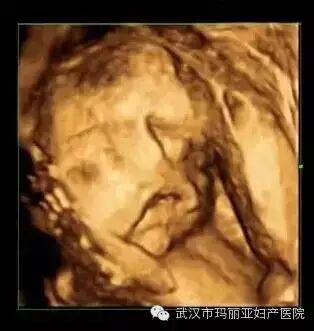

武汉玛丽亚妇产医院引进的世界领先的美国GE-E8四维彩超设备室目前世界上最先进、分辨率最高的彩色超声设备,具有即时立体成像、清晰准确的特点。

它能够多方位、多角度地观察宫内胎儿的生长发育情况,为早期诊断胎儿先天性体表畸形和发育异常提供科学依据。还能对胎儿的体表进行检查,如唇裂、脊柱裂、大脑、肾、 骨骼发育不良等,以便尽早的进行治疗。

玛丽亚目前已拥有三台四维彩超机器设备,是武汉乃至湖北拥有较多台四维彩超的妇产专科医院。四维彩超检查的专业性更强,因此它对操作人员的技术与经验要求很高,也只有准确熟练的手法才能达到最佳的检查效果,才能更好的向让准妈妈准爸爸们展示宝宝人之初的惊艳亮相。